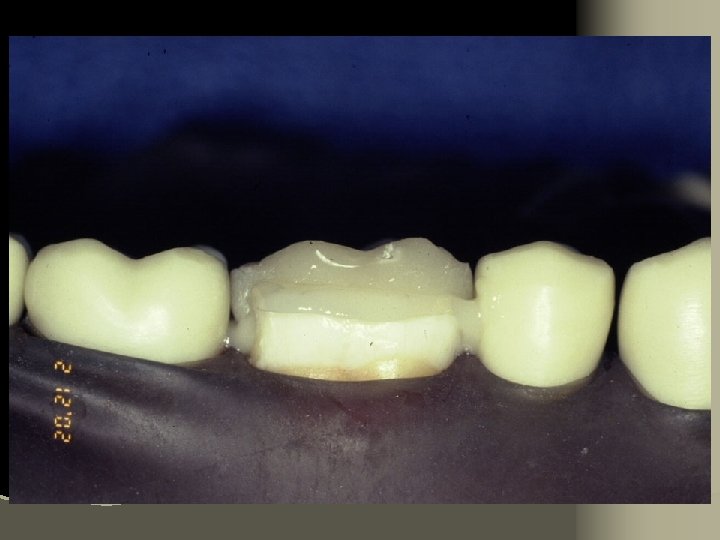

Cementation Procedure 1. Remove temporary and all residue of temporary cement 2. Check occlusion on adjacent teeth (mylar shimstock and articulating paper) 3. Place rubber dam 4. Clean tooth with pumice and rubber cup, rinse and lightly dry 5. Try in restoration for fit.

6. Adjust proximal contacts if necessary 7. Evaluate shade intraorally using water soluble try-in paste (optional) 8. Rinse out try-in paste and air dry 9. Etch inside of restoration (HF porcelain etchant X 2 minutes), rinse with distilled water and air dry 10. Place drop of silane (porcelain primer) on intaglio surface for 1 minute, lightly air thin to evaporate solvent